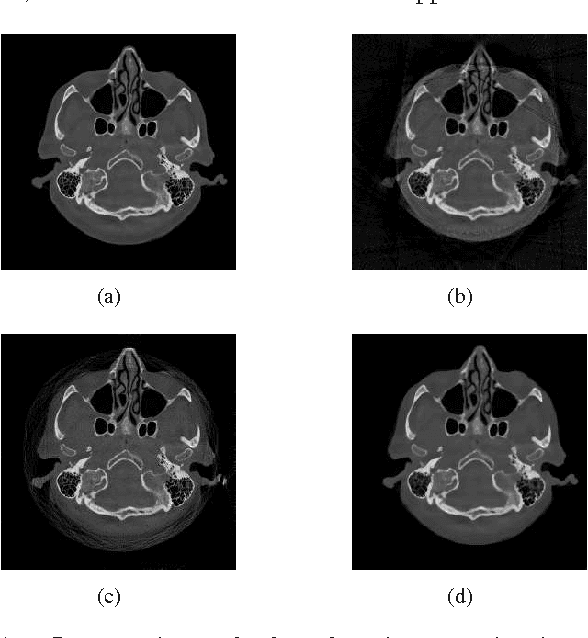

Abstract:When a measurement falls outside the quantization or measurable range, it becomes saturated and cannot be used in classical reconstruction methods. For example, in C-arm angiography systems, which provide projection radiography, fluoroscopy, digital subtraction angiography, and are widely used for medical diagnoses and interventions, the limited dynamic range of C-arm flat detectors leads to overexposure in some projections during an acquisition, such as imaging relatively thin body parts (e.g., the knee). Aiming at overexposure correction for computed tomography (CT) reconstruction, we in this paper propose a mixed one-bit compressive sensing (M1bit-CS) to acquire information from both regular and saturated measurements. This method is inspired by the recent progress on one-bit compressive sensing, which deals with only sign observations. Its successful applications imply that information carried by saturated measurements is useful to improve recovery quality. For the proposed M1bit-CS model, alternating direction methods of multipliers is developed and an iterative saturation detection scheme is established. Then we evaluate M1bit-CS on one-dimensional signal recovery tasks. In some experiments, the performance of the proposed algorithms on mixed measurements is almost the same as recovery on unsaturated ones with the same amount of measurements. Finally, we apply the proposed method to overexposure correction for CT reconstruction on a phantom and a simulated clinical image. The results are promising, as the typical streaking artifacts and capping artifacts introduced by saturated projection data are effectively reduced, yielding significant error reduction compared with existing algorithms based on extrapolation.